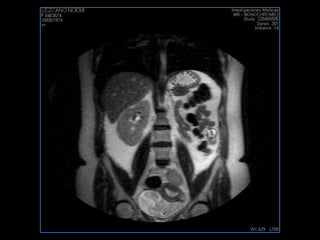

LIC ALEJANDRA GALVEZ RM DE ABDOMEN

resonancia de abdomen